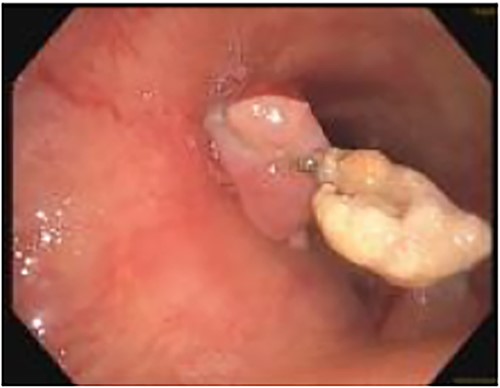

A 71-year-old female presented in May 2020 with a 6-month history of progressive dysphagia and weight loss. Her past medical history was significant for recurrent ductal carcinoma in situ of the left breast. She was a never smoker. Esophagogastroduodenoscopy (EGD) showed a proximal circumferential mass with friable mucosa and ulcerations at 15 cm (Fig. 1A–D). Computed tomography (CT) imaging showed significant soft tissue thickening and luminal narrowing of the esophagus from the sternoclavicular joints to the carina (Fig. 2E). An esophageal stent was placed to support nutrition, which improved the patient’s dysphagia. Biopsy confirmed invasive SCC. Subsequent positron emission tomography imaging revealed 18-fluorodeoxyglucose-avid mediastinal, bilateral supraclavicular, and subdiaphragmatic lymph nodes. Bronchoscopy showed no evidence of tumor invasion into the airway.

(A–D) EDG images showing circumferential esophageal mass with friable mucosa and ulcerations. (E) CT chest showing marked soft tissue thickening with luminal narrowing in the upper esophagus, which extended to a level below the carina.